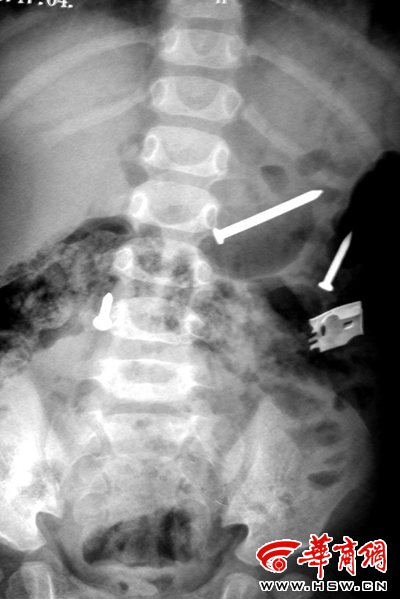

排出鐵釘之后復(fù)檢拍片又顯示肚內(nèi)有鐵釘(劉立春攝)

來(lái)自榆林市米脂縣的這名一歲半女孩,在最近一個(gè)多月內(nèi),從體內(nèi)不斷排出鐵釘,共達(dá)20多枚。更為奇怪的是,在醫(yī)院拍片顯示體內(nèi)已沒(méi)有鐵釘時(shí),過(guò)幾天鐵釘還會(huì)出現(xiàn)。